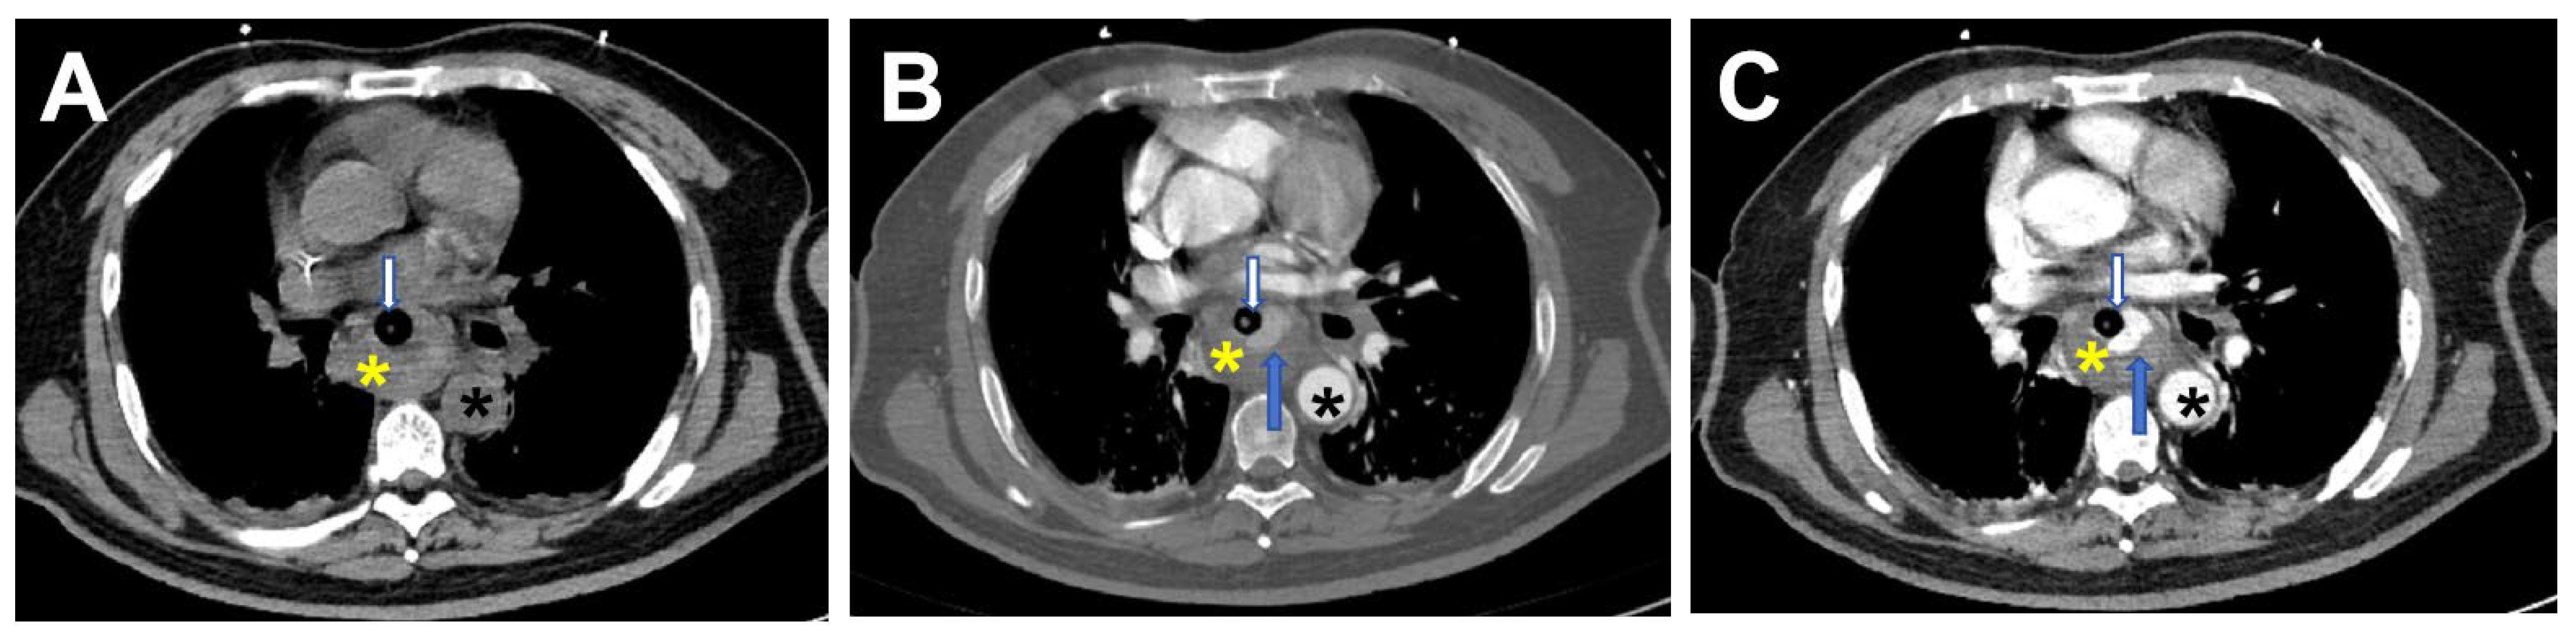

2. Case Report